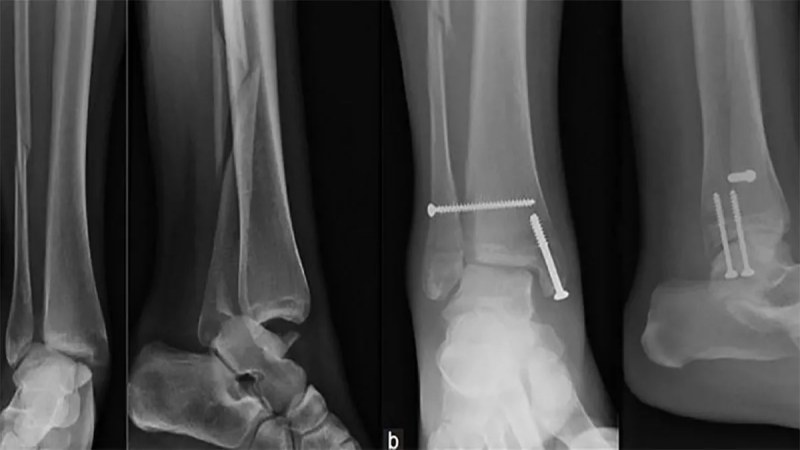

مهمترین و اصلیترین گزینه برای تشخیص شکستگی قوزک پا، عکس رادیولوژی ایکس ری است. در عکس شکستگی مچ پا، صرفاً بافتهای استخوانی قابل رویت است؛ بنابراین برای تشخیص پیچ خوردگی یا شکستگیهای بسیار کوچک باید از تصویربرداریهایی با جزئیات بیشتر مثل MRI و سیتیاسکن استفاده شود.

- جراحی: در موارد شدیدتر، پزشک طی عمل جراحی از میلهها، پیچ یا صفحات فلزی برای تراز مجدد استخوان استفاده میکند تا در طی بهبودی، استخوانها در وضعیت صحیح قرار بگیرند و جوش بخورند.

- تصویربرداری اشعه ایکس ری: تصویر رادیولوژی، میزان و نوع شکستگی را بهخوبی نشان میدهد.